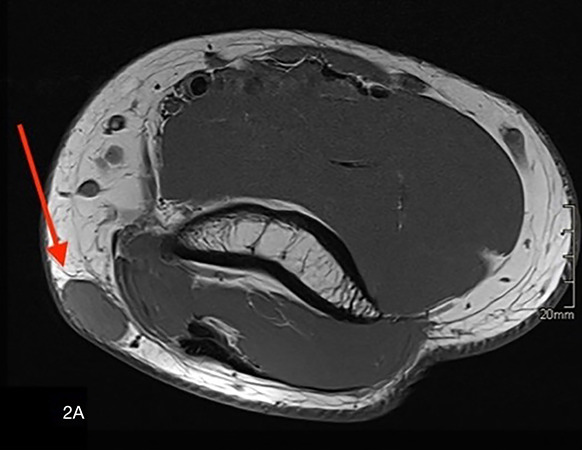

Extradigital Glomus Tumor at the Elbow.

Teaching point: Extradigital glomus tumor should be considered in the differential diagnosis of a highly vascular solid lesion that is painful on palpation.